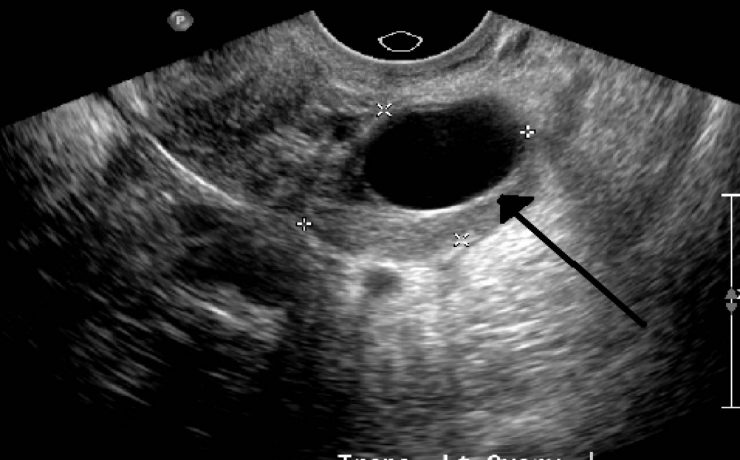

Mastitis granulomatosa idiopática

La mastitis granulomatosa idiopática es un proceso inflamatorio mamario benigno, poco frecuente, de origen desconocido. Se presenta en mujeres en edad reproductiva, entre los 17 y 42 años de edad. El diagnóstico se realiza por exclusión; para ello se utiliza ultrasonido, biopsia por aspiración de aguja fi na o biopsia